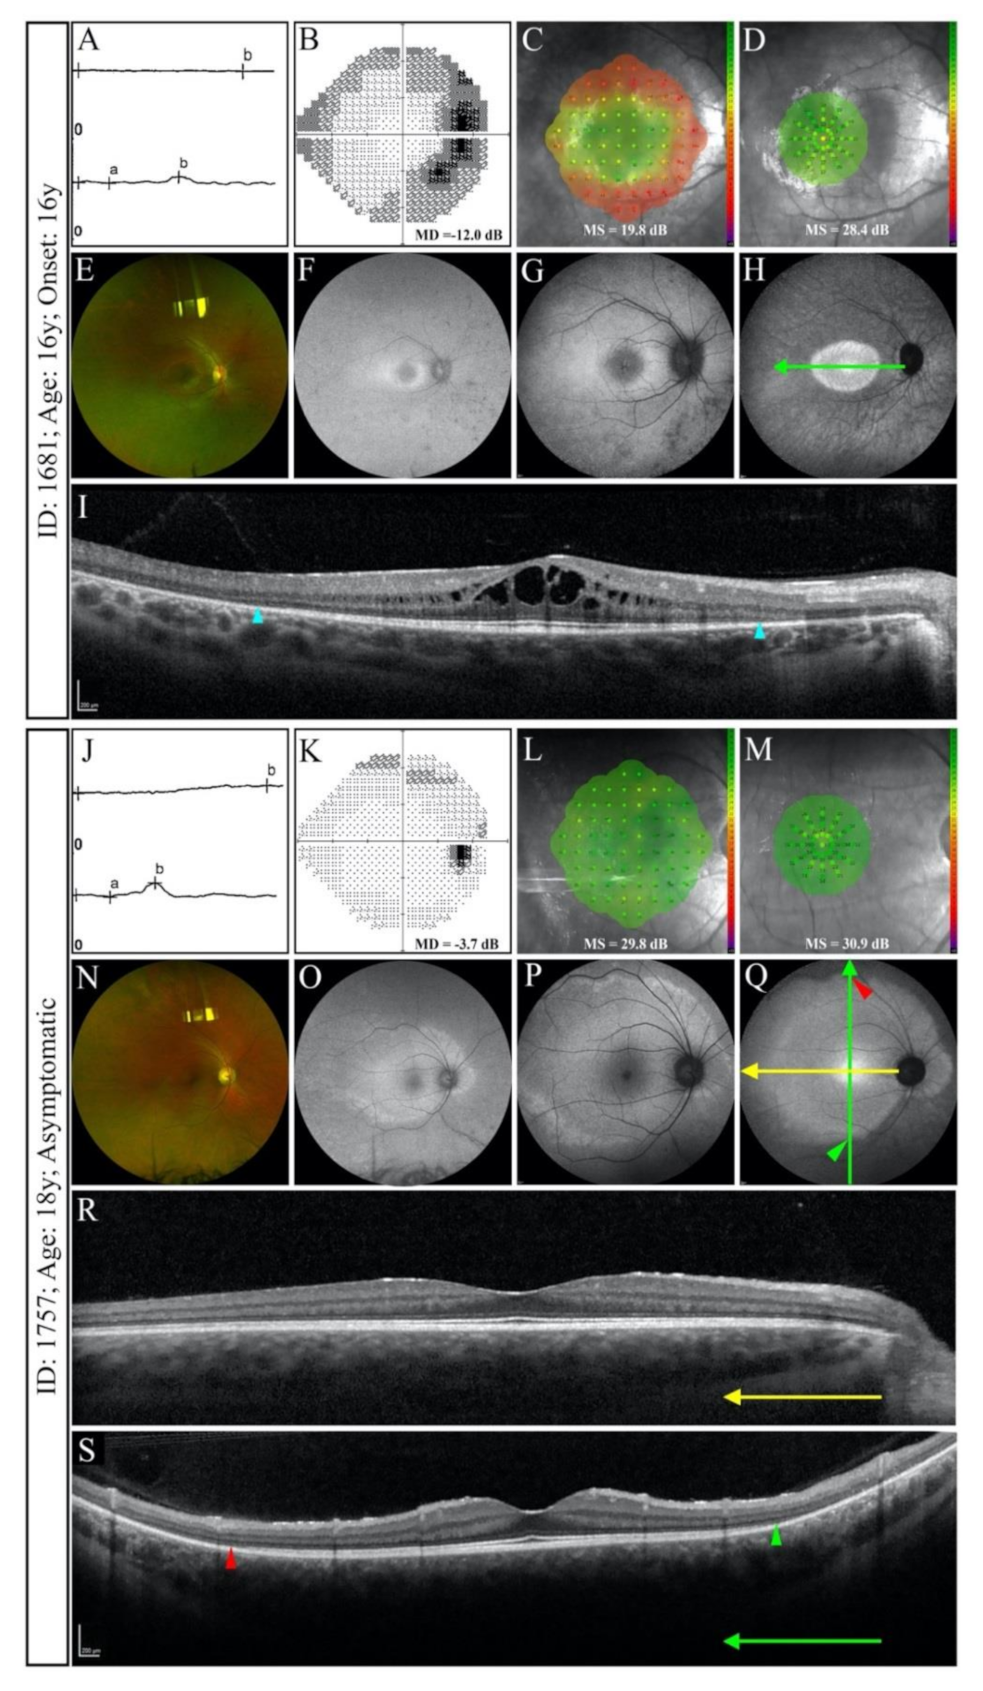

3.2. Baseline Clinical Features

3.2.2. Splice Site Mutations

3.4. Phenotype Patterns

4. Discussion

4.1. RP11 Phenotype Varies in Patients with Identical or Similar Mutations